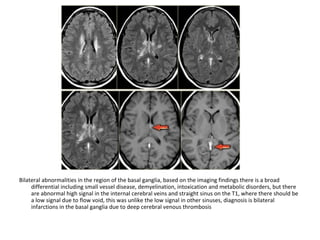

Bilateral abnormalities in the region of the basal ganglia, based on the imaging findings there is a broad

differential including small vessel disease, demyelination, intoxication and metabolic disorders, but there

are abnormal high signal in the internal cerebral veins and straight sinus on the T1, where there should be

a low signal due to flow void, this was unlike the low signal in other sinuses, diagnosis is bilateral

infarctions in the basal ganglia due to deep cerebral venous thrombosis